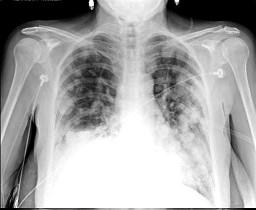

问题 女,51岁,胸闷、咳嗽、咳痰,3年前被确诊为子宫平滑肌肉瘤,请结合胸片选出最可能的诊断()

选项 A.粟粒性肺结核 B.肺转移瘤 C.结节病 D.胶原病 E.真菌病

答案 B